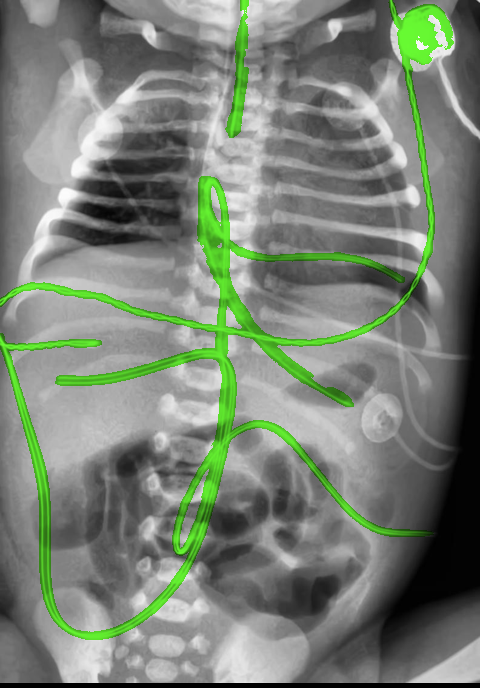

Automated catheter detection is a challenging task. Although most catheters have a radiopaque strip to facilitate detection, the strip may become less apparent depending on the projection angle. Catheters maybe confused by other similar linear structures like ECG leads and anatomy including ribs. Additionally, portions of catheters can be occluded by anatomical structures given that radiographs are a 2D projection of a 3D structure. For example, when a NGT is placed within the oesophagus, the catheter itself becomes less apparent due to the high density of the adjacent vertebrae. Finally, the number and type of catheters that could possibly appear in pediatric X-rays are unknown a priori. The catheters may be intertwined with each other thus making simple line tracing methods fail. Figure 1 gives three sample pediatric X-ray images with some common catheters highlighted in different colors.

To alleviate this annotation problem in catheter detection, we proposed to use X-ray images with simulated catheters by exploiting the fact that catheters are essentially tubular objects with various cross sectional profiles. To be more specific, a synthetic 2D projection of a catheter is generated by first simulating a horizontal catheter profile and then using it as a brush tip to draw along a B-spline path. This generated catheter is then composited with an X-ray image serving as the training data. Another contribution of this work is a segmentation network that can inherently take into account multi-scale information. This network adopts a UNet-style form and contains a recurrent module that can process inputs with increasing scales111Our code is available at https://github.com/xinario/catheter_detection.git.. We have empirically shown that by iterating through the scale space of the input image, higher recall is achieved as compared to using a single scale. Details about the methods are discussed in Section 3. Three sample detection results are shown in Figure 1.

The test dataset is collected locally and only contains frontal chest-abdominal X-rays from patients < 4 weeks old. This is the most common radiograph obtained to confirm placement of catheters such as UACs and UVCs in neonates. Currently, the test set has 35 fully labeled images with different catheter types with sample images previously shown in Figure 1. All the annotated catheters (lines excluding ECG leads) are treated as the same class in the detection.